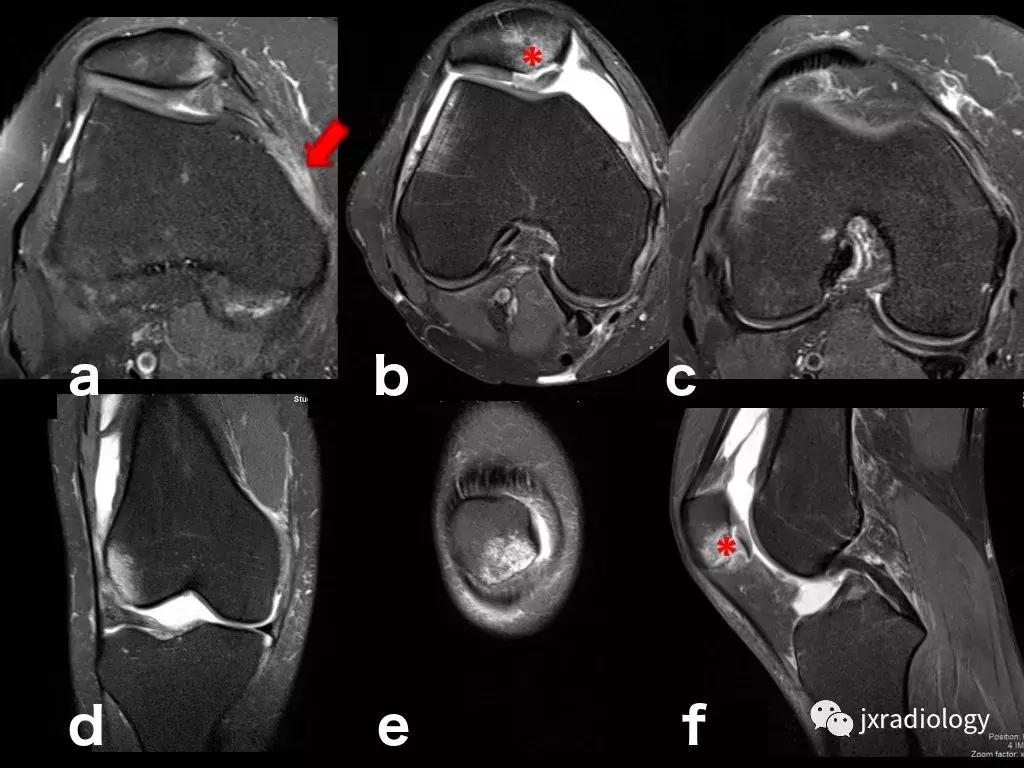

图8:创伤性骨髓水肿,髌骨脱位的典型病例:青年人,髌骨一过性脱位和挫伤的横断面(a,b,c),冠状面(d,e)和矢状面(f)的PD-FS-WI图像 :股骨外侧髁的前外侧和髌骨下内侧的故事水肿。对于进行运动的青少年或年轻人来说,在弯曲时需要膝盖扭转运动的情况更为常见。如该患者患有髌骨骨软骨损伤(*)和内侧髌股韧带(MPFL)撕裂(箭头)。